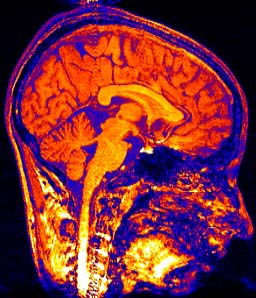

NEUROBIOLOGY : ‘neuro-‘ refers to the nervous system, which includes the brain. So,

the biology of the nervous system.

In his introduction, Siegel attempts to lay a foundation for the dense neurobiological and neuropsychological discussion to follow. At the heart of his message, which he reiterates again and again, is that “the mind emerges from the activity of the brain, whose structure and function are directly shaped by interpersonal experience” (p.1) and that his book hopes to “build a foundation for a neurobiology of interpersonal experience.” (p.1)

1. The human mind emerges from patterns in the flow of energy and information within the brain and between brains.

2. The mind is created within the interaction of internal neurophysiological processes and interpersonal experiences.

3. The structure and function of the developing brain are determined by how experiences, especially within interpersonal relationships, shape the genetically programmed maturation of the nervous system.” (p.2)

“By altering both the activity and the structure of the connections between neurons, experience directly shapes the circuits responsible for such processes as memory, emotion and self-awareness. We can use an understanding of the impact of experience on the mind to deepen our grasp of how the past continues to shape present experience and influence future actions.” (p.2)